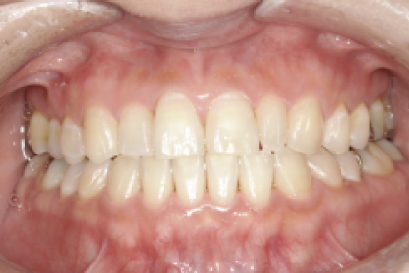

術前

術後

年代、性別

10代、女性

職業

学生

主訴

歯並び相談

部位

インビザラインによる全顎矯正

治療期間

6ヶ月

矯正費用

95万円

施術説明

インビザラインによる全顎矯正。成人式まで期間がない中、綺麗な写真で成人式を祝いたいという事でお母様と来院されました。見た目への支障で悩んでいましたが、検査の結果アライナー矯正が可能と判断し半年で矯正を完了できました。成人式の記念撮影にも間に合い、非常に喜んで頂けました。

副作用・リスク

なし